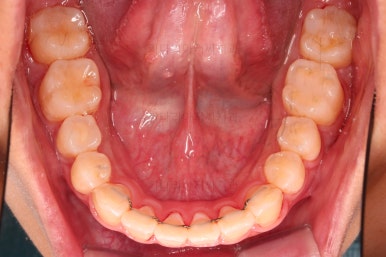

1. 초진 시 입안의 모습 평가

부산연산역치아교정 키다리아저씨치과에 처음 내원했을 당시의 입안의 모습이비다.

앞니 약간, 어금니쪽 약간 삐뚤어진 것, 그리고 위아래 앞니가 약간 뻗쳐 보이는 양상 이외에는 매우 가지런해 보여서 교정치료를 굳이 왜 하시려고 하지? 라고 생각될 정도의 치열 상태였습니다.